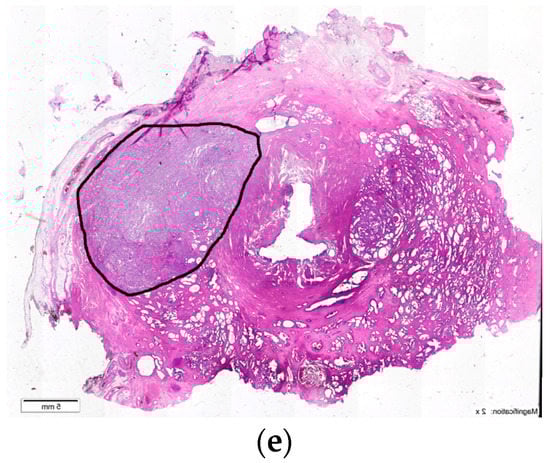

10. Prostatic Abscess